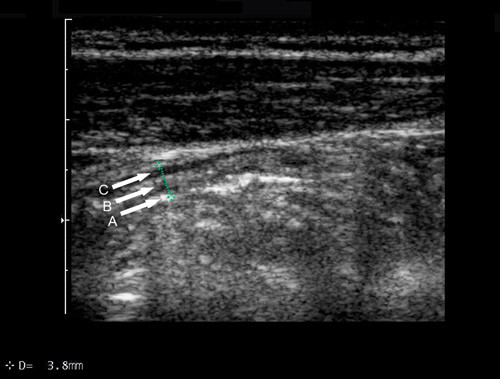

Med høyfrekvent ultrasonografi ses vanligvis fem lag i en normal tarmvegg (6, 7) enten man vurderer veggen fra serosa (transdusernære tarmvegg) eller fra mucosasiden (dorsale, transduserfjerne tarmvegg) (fig 1). Hvis det ses færre eller flere enn fem vegglag, kan dette indikere sykdom. For å undersøke om et tarmavsnitt er patologisk eller ikke, måles blant annet tarmveggens tykkelse. Lagdelingen i tarmveggen gjør at det oppstår overgangsekko når ultralydbølgene passerer fra et vegglag til et annet. Tykkelsen av tarmveggen måles oftest av den ventrale, transdusernære tarmveggen og vil da inkludere lagene 2 – 4, siden lag 1 i dette tilfellet er overgangsekkoet mellom lumen og mucosa. Overgangsekkoet mellom serosa og muscularis propria vil dessuten dekke en liten del av muscularis propria og således føre til at ventralsiden fremstår noe tynnere enn dorsalsiden med ultralyd. Siden dorsalsiden ofte er vanskelig å fremstille, velger man imidlertid ventralsiden som utgangspunkt for målingene.